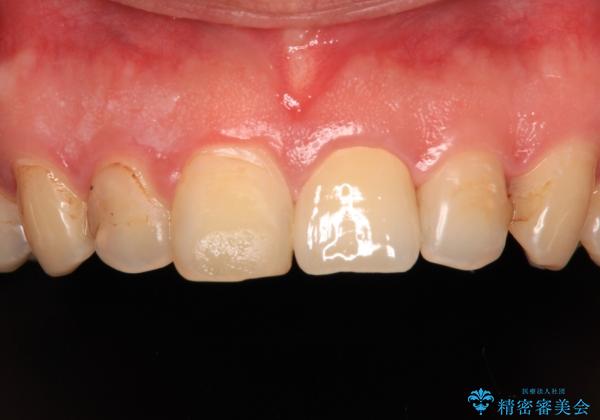

- 前歯の色を気にして来院された患者様です。

むし歯で神経が取り除かれており、歯の変色と充填材の変色などにより、つぎはぎのような前歯となっていました。

膿の出口も認められたため、まずは根管治療を実施し、オールセラミッククラウンにて補綴治療を行うこととしました。